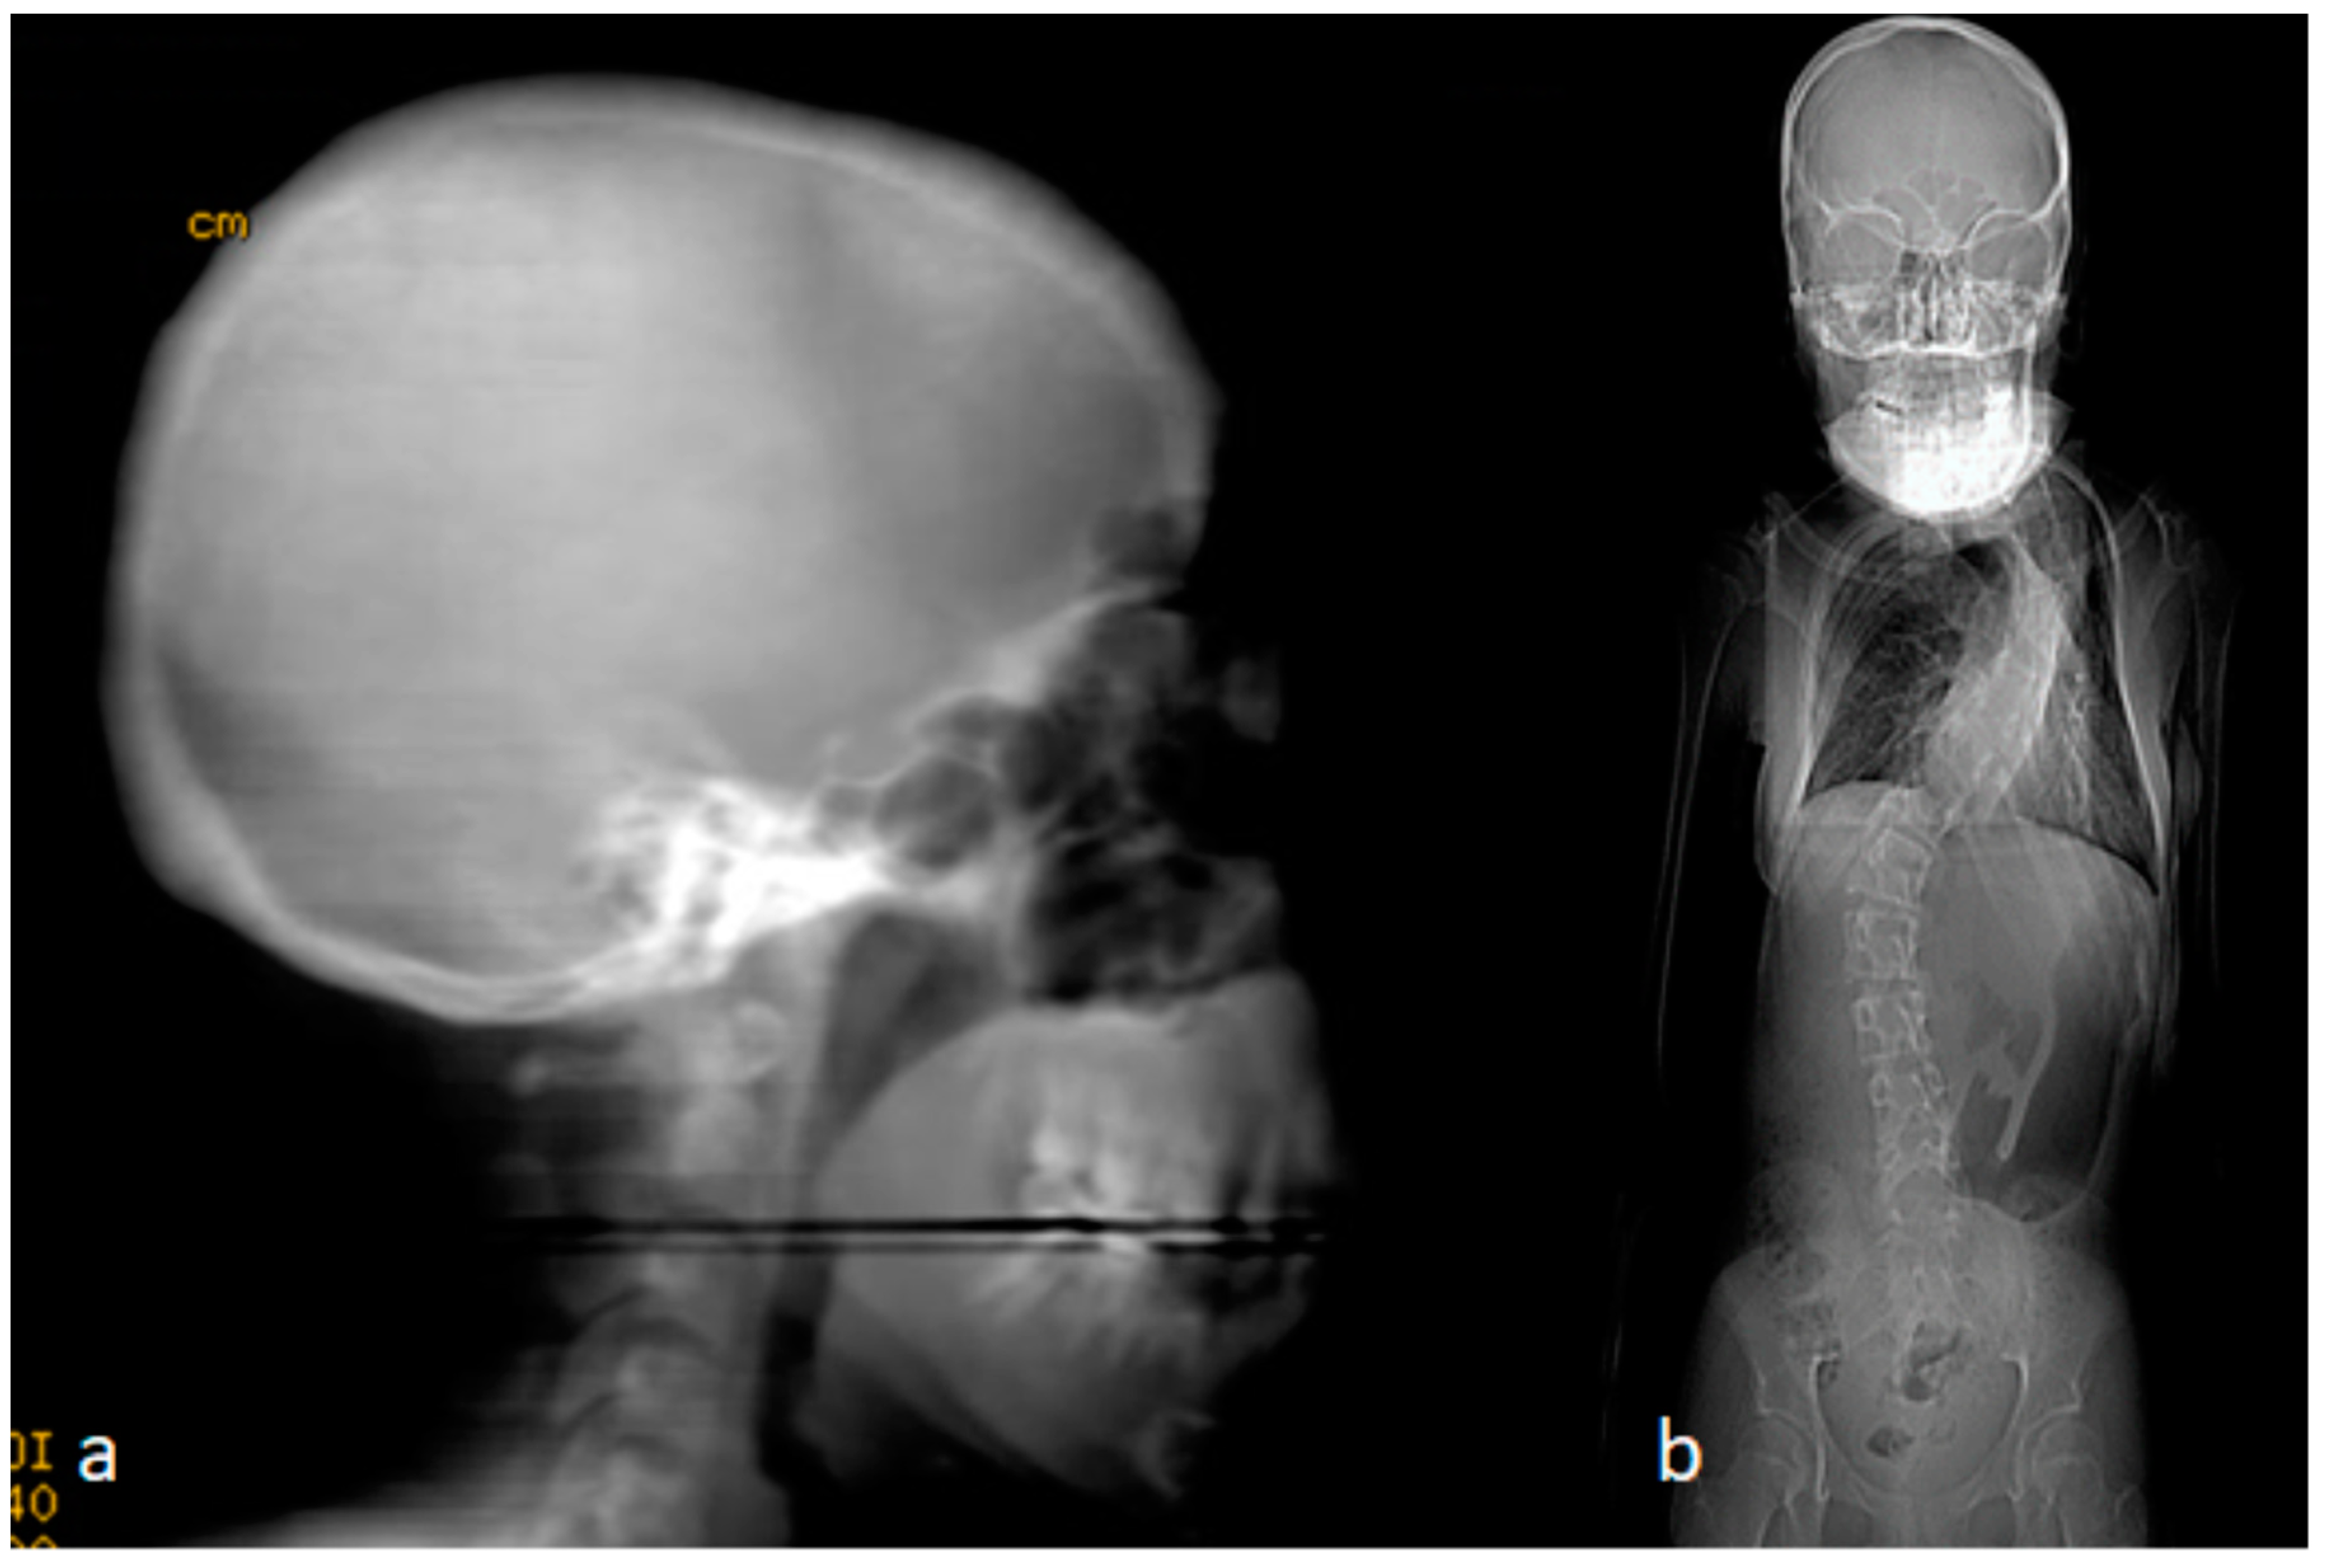

Clinical documentation and radiological documentation are shown in Figure 1a,b. The clinical photo showed craniofacial dysmorphic features, marfanoid habitus, long and thin limbs, arachnodactyly, intellectual disability, and scoliosis of 65° of Cobbs angle, and a Milwaukee brace was prescribed to prevent further spine tilting (Figure 1a). The lateral skull radiograph showed scaphocephaly (the skull is of abnormal contour, showing a bilateral narrow head because of premature closure of the sagittal suture). The synostosed sagittal suture formed a well-palpated osseous ridge (Figure 1b).

Figure 1. (a,b). The clinical phenotype of an 11-year-old child referred to the senior author with a diagnosis of pre-pubertal idiopathic scoliosis. Clinically, he manifested craniofacial dysmorphic features, marfanoid habitus, long and thin limbs, arachnodactyly, intellectual disability, and scoliosis of 65° of Cobbs angle (a). Lateral skull radiograph showed scaphocephaly (the skull is of abnormal contour and appeared narrow because of premature closure of the sagittal suture). The sagittal suture formed a well-palpated osseous ridge (b).